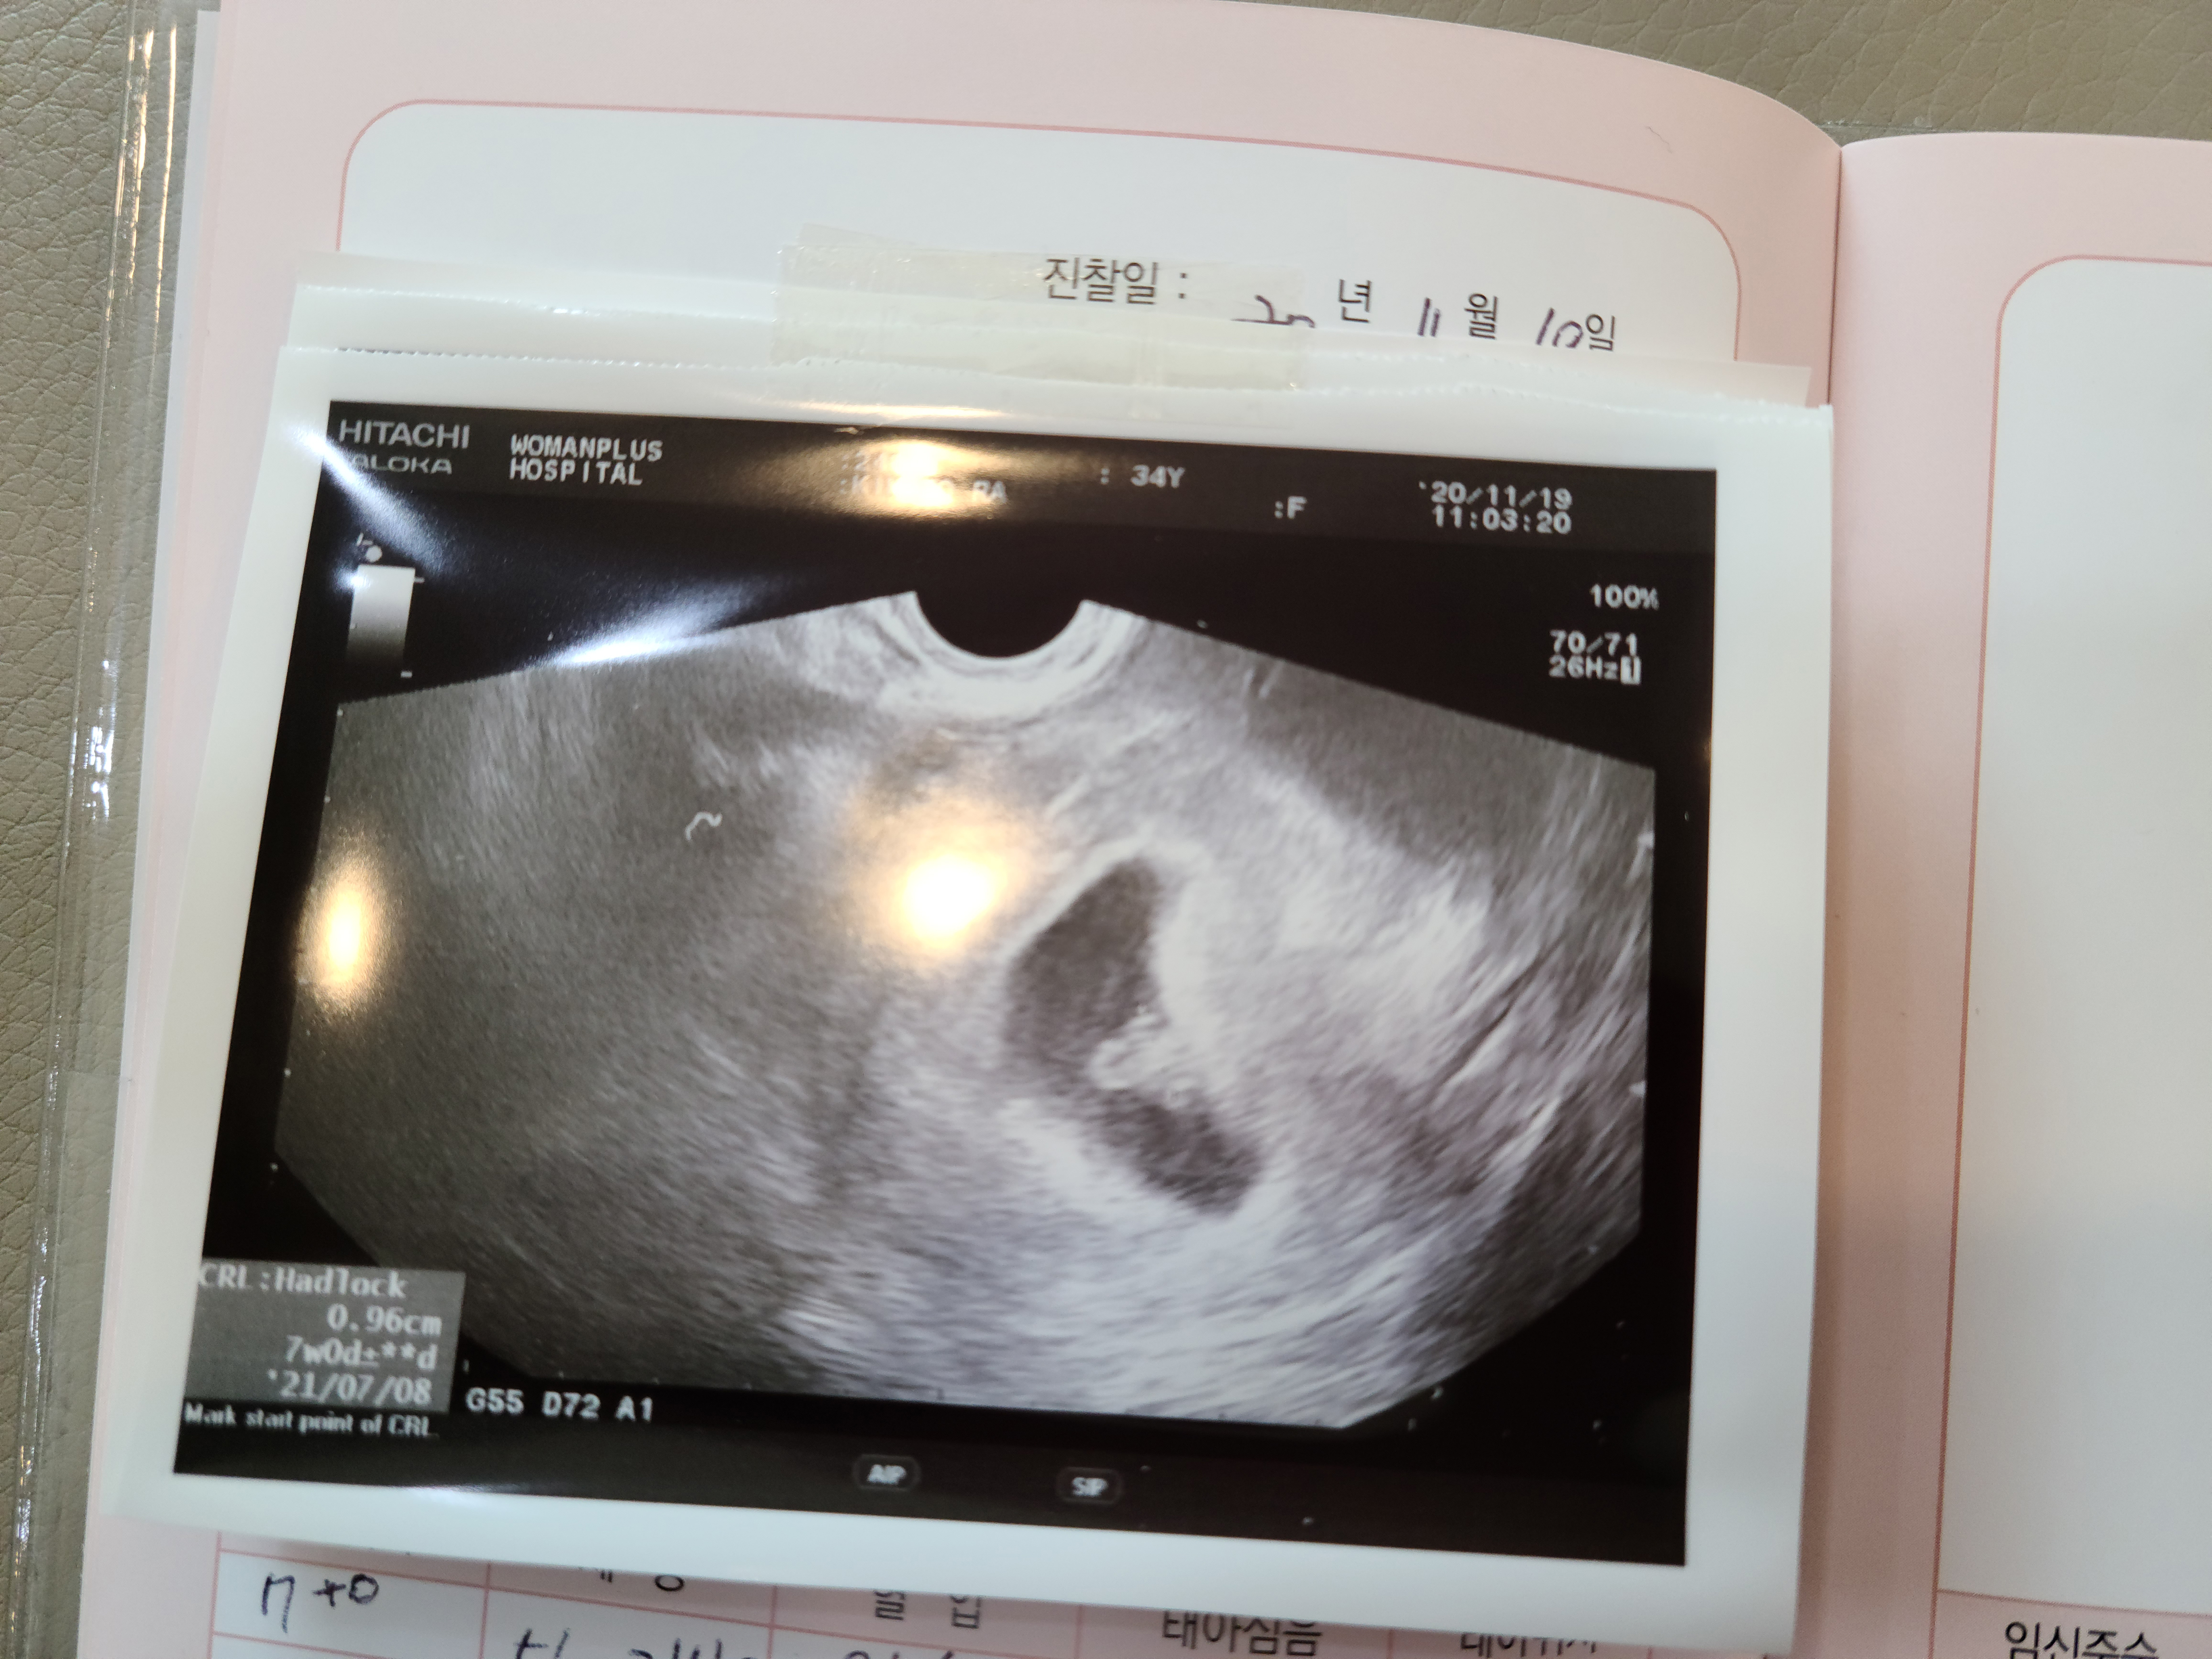

세번째, 무탈이의 심장이 뛰는 소리를 들었을 때,

엄마와 아빠는 너무 감격스럽고 기뻐 심장이 뛴다.